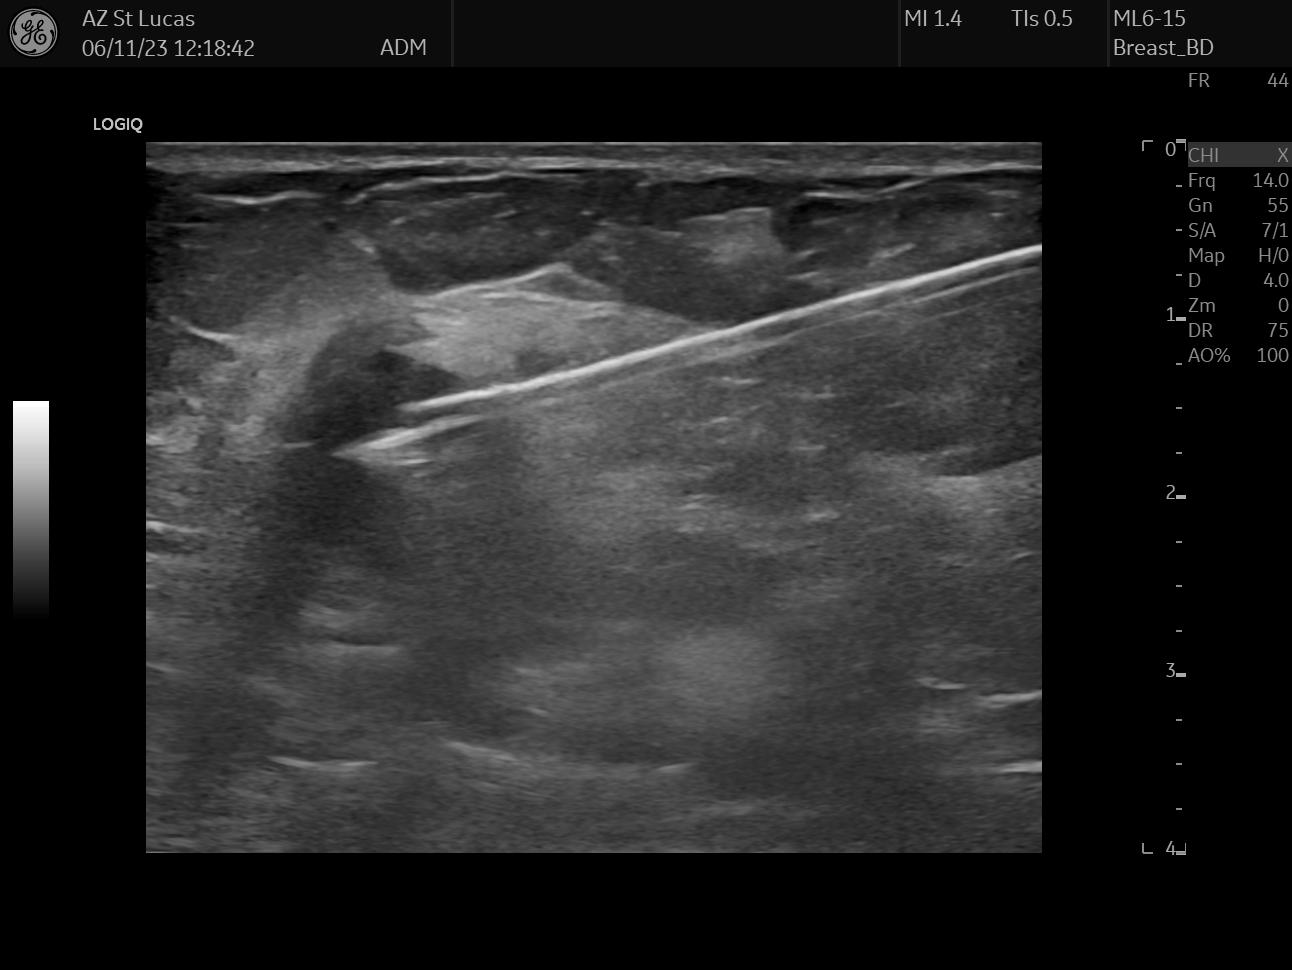

On October 17th 2023 I went to the hospital for an echography; the radiologist asked me almost immediately if they could perform a biopsy. So they stuck a needle in my breast and took out a few tissue samples. It was painful as hell and I ended up crying, confused, and trembling on the bed. The doctor asked me why I went alone for a check of this entity. Well, I didn’t know better, but there was my first lesson:

The data I chose for this day are two scans from the echography, they both clearly show the lesion; the second picture also shows the measurements the radiologist took.

At this point of the ordeal we still needed to take care of two things, and both of these had to do with implanting stuff in my body. The first thing we inserted was a little clip in my breast, a tiny titanium marker used to pinpoint the exact position of the tumor. If we were going, hopefully, to kill the whole tumor, the clip was going to guide the surgeon find the correct area for removal later on. Furthermore, the clip was going to be monitored during imaging exams in the course of chemotherapy to understand changes over time.

This procedure happens with the same principle of a biopsy: a needle is inserted in the breast, but instead of taking tissue material away, the needle leaves the small clip behind. In the records I have selected from this procedure you can see the lesion in my breast, the long needle inside it, and eventually the clip in the middle of the tumor.